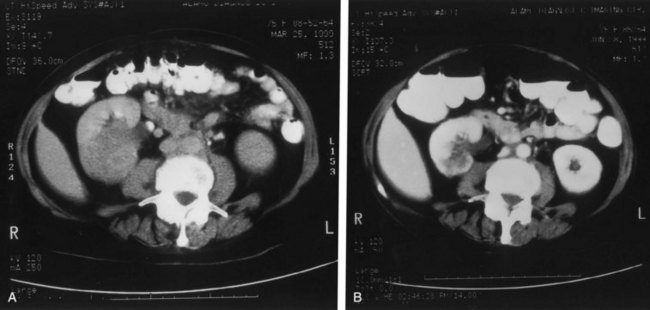

Although intravenous pyelography has been the traditional means for diagnosis of upper tract lesions, computed tomographic (CT) urography is increasingly performed today. CT is easier to perform and less labor intensive than intravenous pyelography. It also has a higher degree of accuracy in determining the presence of renal parenchymal lesions. On the other hand, small urinary filling defects (<5 mm) may be missed between the “cuts” of the traditional CT scan. More recently, CT urography has been performed to obtain a three-dimensional image of the upper tracts. This technique appears to be equal to intravenous pyelography in imaging the ureters and renal pelvis (McTavish et al, 2002). With CT urography, the sensitivity for detecting upper tract malignant disease has been reported to approach 100%, with a specificity of 60% and a negative predictive value of 100% (Caoili et al, 2002). CT urography does, however, expose the patient to higher doses of radiation.

Radiolucent filling defects, obstruction or incomplete filling of a part of the upper tract, and nonvisualization of the collecting system are the typical findings suggestive of an upper urinary tract tumor. Filling defects, which account for 50% to 75% of cases, typically require the intravenous administration of contrast material to be identified (Murphy et al, 1981; Fein and McClennan, 1986). The differential diagnosis of these defects includes blood clot, stones, overlying bowel gas, external compression, sloughed papilla, and fungus ball. Stones can be ruled out most easily by confirmation of calcification by renal ultrasonography or CT. TCCs have an average density of 46 Hounsfield units (HU) and a range of 10 to 70 HU (Lantz and Hattery, 1984). This is in contrast to an average of 100 HU seen in radiolucent uric acid stones (range, 80 to 250 HU). Thus CT can be useful in distinguishing between these two common causes of radiolucent filling defect on excretory urography or retrograde ureterography. The impact of hydronephrosis and nonvisualization for renal pelvis tumors versus ureteral tumors as indicators of a higher stage is uncertain. Nonvisualization is reported in 20% of renal pelvis tumors, only 33% of which are invasive (McCarron et al, 1983). Nonvisualization is reported in 37% to 45% of ureteral tumors and carried a 60% risk of invasion in one series (McCarron et al, 1983). In other reports there is no correlation of nonvisualization and stage (Batata and Grabstald, 1976; Anderstrom et al, 1989). Hydronephrosis with or without an associated filling defect is linked with invasion in 80% of ureteral tumors (McCarron et al, 1983; Cho et al, 2007).

Some have suggested that ultrasonography has sensitivity equal to that of urography in evaluating patients with painless gross hematuria for upper tract malignant disease (Yip et al, 1999; Data et al, 2002). For staging purposes, CT or magnetic resonance imaging (MRI) is most useful in determining the extent of invasion, an associated mass lesion outside the collecting system, and the presence of lymph node or distant metastases (Milestone et al, 1990). CT is also more sensitive than conventional radiography in determining minimally radiopaque substances, making it useful in identifying urine excreted by poorly functioning areas of kidney (as in obstructed areas) (Kenney and Stanley, 1987). The greatest downside of CT or MRI is in the detection of small lesions that may be lost in volume averaging. In one series, CT predicted TNM stage in 60% of patients; it understaged 16% and overstaged 24% (Scolieri et al, 2000).